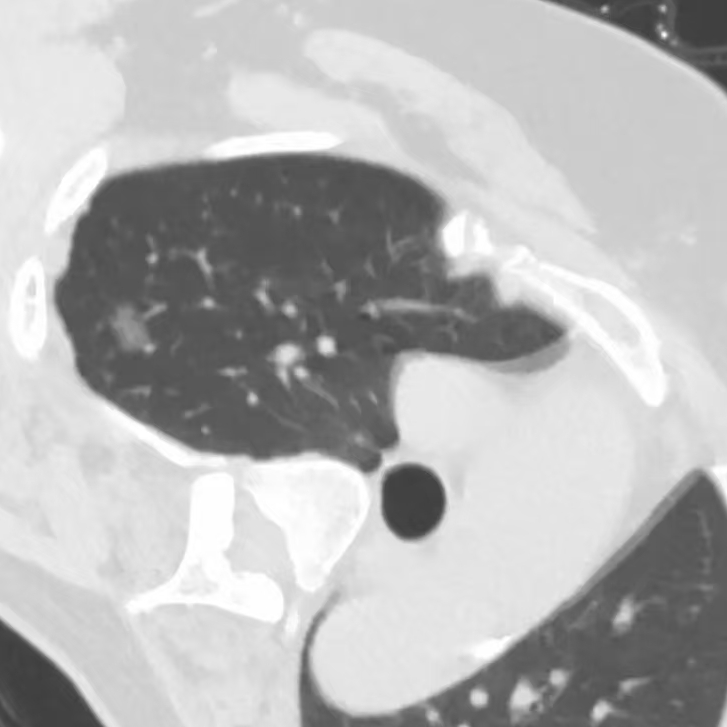

健康直通车: 健康是生命的宝贵财富,也是幸福生活的基石。为了更好地服务广大百姓,传播健康知识,葫芦岛市第二人民医院推出“健康直通车”专题栏目,将专业的医学知识以通俗易懂的方式传递给每一位市民,掌握科学的疾病预防方法,共同构筑健康中国的坚实基石。 什么是肺结节 肺结节是指肺内直径小于或等于3cm的类圆形或不规则形病灶,影像学表现为密度增高的阴影。大于3cm的称肿块。肺结节依其密度不同可分为实性结节、部分实性结节、磨玻璃结节,其中部分实性结节的恶性可能性最大,磨玻璃结节次之,实性结节尤其是小的实性结节结节最可能是良性的。 肺结节的常见病因 1、良性(约90%) 🔸 感染:结核、真菌、细菌性肺炎后遗留的瘢痕; 🔸 非感染:错构瘤(良性肿瘤)、炎性假瘤、血管瘤等。 2、恶性(约10%) 🔸原发性肺癌(如腺癌、鳞癌); 🔸转移性肿瘤(其他器官癌症转移至肺)。 如何根据影像判断肺结节性质 1、依据结节大小判断 🔸小于0.5cm的肺结节绝大多数都是良性的,属于微小结节。即使部分小于0.5cm肺结节是恶性的,但是适当的观察不影响预后。每年复查一次胸部CT就可以。 🔸大于0.5cm持续存在的纯磨玻璃结节,观察6个月,若持续存在,不管有无进展均多数是恶性的,视患者意愿,手术可以立即做也可观察至进展再做,不影响预后。 🔸大于0.8cm的部分实性结节恶性可能性非常大,应积极评估结节边缘毛刺、分叶、胸膜凹陷等征象。 🔸若实性部分大于0.5cm,恶性率显著提高。若在3~6个月随访期间实性部分增大或者总体部分增大,都可以考虑手术切除。而即使小于0.8cm的部分实性结节也需3个月就复查对比。 2、依据肺结节形态 如CT上提示病灶形态不规则、毛刺、分叶、胸膜凹陷、空泡征、血管集束征等,符合恶性肿瘤的征象。 🔸结节与正常肺组织之间界限非常清楚的恶性可能性大。 🔸结节密度不均呈混杂密度或均匀较大纯磨玻璃结节也基本是恶性的。 🔸有胸膜牵拉(不管是肺表面的脏层胸膜还是叶间裂部位的胸膜)的恶性可能性大。 🔸结节有浅分叶、细毛刺,密度较高而与周围肺组织边界不清的恶性可能性大。 🔸磨玻璃或混合磨玻璃结节存在小空洞的恶性可能性大。 🔸影像上似慢性炎表现,而没有炎症相关的其他异常,特别当所谓炎症区域内部或一侧与正常肺组织之间界限非常清楚的基本上是恶性的。 3、从结节发展情况来看 所有随访中增大进展的都需要考虑恶性可能,不进展而持续存在的纯磨玻璃结节也需考虑恶性。 葫芦岛市第二人民医院肺结节诊治中心孙振教授深耕肺结节领域四十余载,凭借对临床实践的执着钻研与深厚积淀,在肺结节精准诊断及鉴别诊断领域形成独到见解。他系统总结海量临床病例,创新性提炼出一套科学化、规范化的肺结节全周期诊疗体系,尤其在早期微小结节的影像特征识别、良恶性风险分层等方面积累了丰富经验,为众多患者提供了精准、高效的诊疗方案。 人民医院·人民名医 孙振 主任医师 三级教授 ·葫芦岛市第二人民医院胸外科主任、肺结节诊治中心主任 ·中国医科大学客座教授 ·原央企总医院著名胸外科专家 ·辽宁省医学会胸外科委员 ·辽宁省抗癌协会肺癌专业委员会委员 ·辽宁省细胞生物学学会食管癌专业委员会理事 ·主持多项科研成果获科技成果奖、科技进步奖、国家专科奖项 医学成就 从事胸外科临床工作近40年,担任胸外科首席专家及科室主任20余年,是我省胸外科领军人物,推动肺癌、食管癌等胸部肿瘤外科的规范化诊疗,在央企总医院牵头成立了肺结节诊疗中心,率先开展CT引导下肺内小结节定位切除,既确切完整切除肺内小结节,又降低肺功能损害。 专业特色 擅长肺癌、食管癌的外科手术和综合治疗,在各类高难度胸外伤手术治疗、胸腔镜微创手术、胸腺瘤手术及复杂并发症处理方面具有高深造诣,尤其擅长肺癌早期诊断,胸部小结节CT早期肺癌的鉴别等。完成各类高难度胸外科手术5000余例,其中微创手术占比达90%,治愈率达98%,多项业务填补省内空白。 开展的高难手术 胸腔镜肺部结节微创手术、肺癌根治术、食管癌根治术、各种纵隔肿瘤切除术、胸骨后甲状腺手术及胸部复合性外伤的抢救手术等。